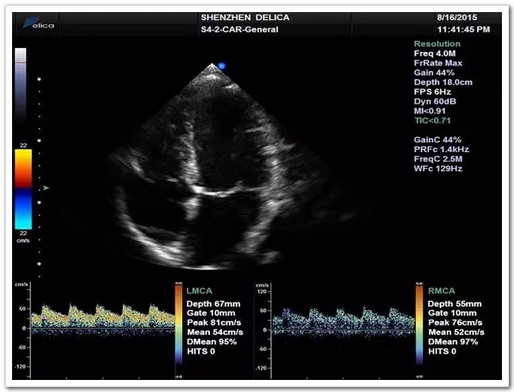

张阿姨血管评估并未发现头颈部血管狭窄的证据,考虑原因不明性卒中,进一步行TCD发泡试验:提示发泡试验阳性-支持右向左分流(固有型,大量)。建议完善经食道心脏超声。

图3:TCD发泡实验(平博网页版,平博(中国)平博(中国))

经食道心脏超声:提示卵圆孔未闭(PFO),裂缝宽约3mm。

至此,张阿姨脑梗死的病因罪魁祸首考虑来自于心脏卵圆孔未闭。TCD发泡试验可以帮助寻找这类病因。